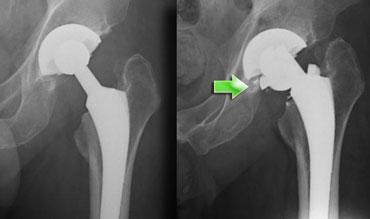

Di lệch cấu phần có giá trị chẩn đoán tình trạng lỏng khớp.

Biểu hiện là sự nghiêng hoặc di lệch lên trên của ổ cối nhân tạo, hoặc sự lún xuống (>10mm) và nghiêng varus của cán khớp háng.

Trường hợp bên trái cho thấy tình trạng lún xuống tiến triển, có giá trị chẩn đoán tình trạng lỏng khớp, kèm theo gãy vít tiếp theo sau đó.

Vì sự di chuyển có thể rất tinh tế, cần so sánh cẩn thận với phim chụp sau phẫu thuật ban đầu.

Không chỉ so sánh với lần khám trước đó.

Trường hợp bên trái cho thấy sự di chuyển của chỏm acetabulum, điều này sẽ được nhận thấy rõ hơn nếu sử dụng một điểm tham chiếu (xem hình tiếp theo)

Nếu chúng ta quan sát các phim X-quang tương tự và sử dụng hình giọt nước mắt làm mốc giải phẫu, sự di trú sẽ trở nên rõ ràng hơn.

Sự di trú của chỏm lên phía đầu đã dẫn đến gãy thành ổ cối (mũi tên xanh).

Sự di chuyển của các thành phần ổ cối là không bao giờ được chấp nhận.

Nó được nhận thấy như sự di chuyển lên trên hoặc nghiêng của chỏm (hình)